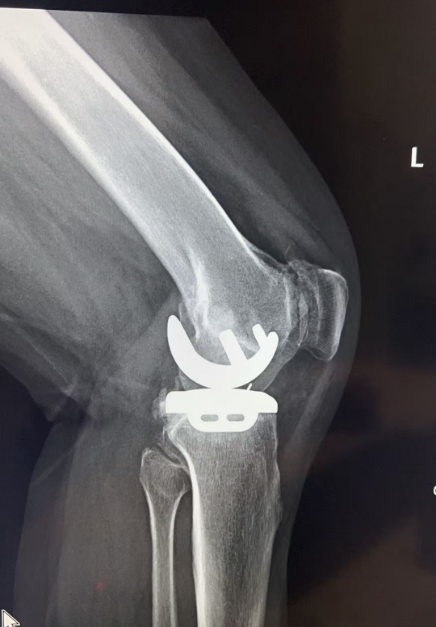

经过仔细评估,王歆峰主任决定给王阿婆做「左膝内侧单髁表面置换术」!这就是保膝治疗的一种,简单说,就是只修复膝盖磨损的那一部分,不用把整个膝盖关节换掉。手术很顺利。

保膝治疗,就像是给磨损的膝盖「修修补补」,而不是「全盘替换」。它针对的是膝盖局部磨损的部位,保留膝盖其他健康的组织和功能。

像王阿婆这样的中老年人,膝盖疼反反复复,确诊为膝关节骨性关节炎,而且磨损主要集中在膝盖的一侧,没有严重的畸形,大多都适合保膝治疗。当然,具体能不能做,还得医生经过详细检查和评估后才能确定。